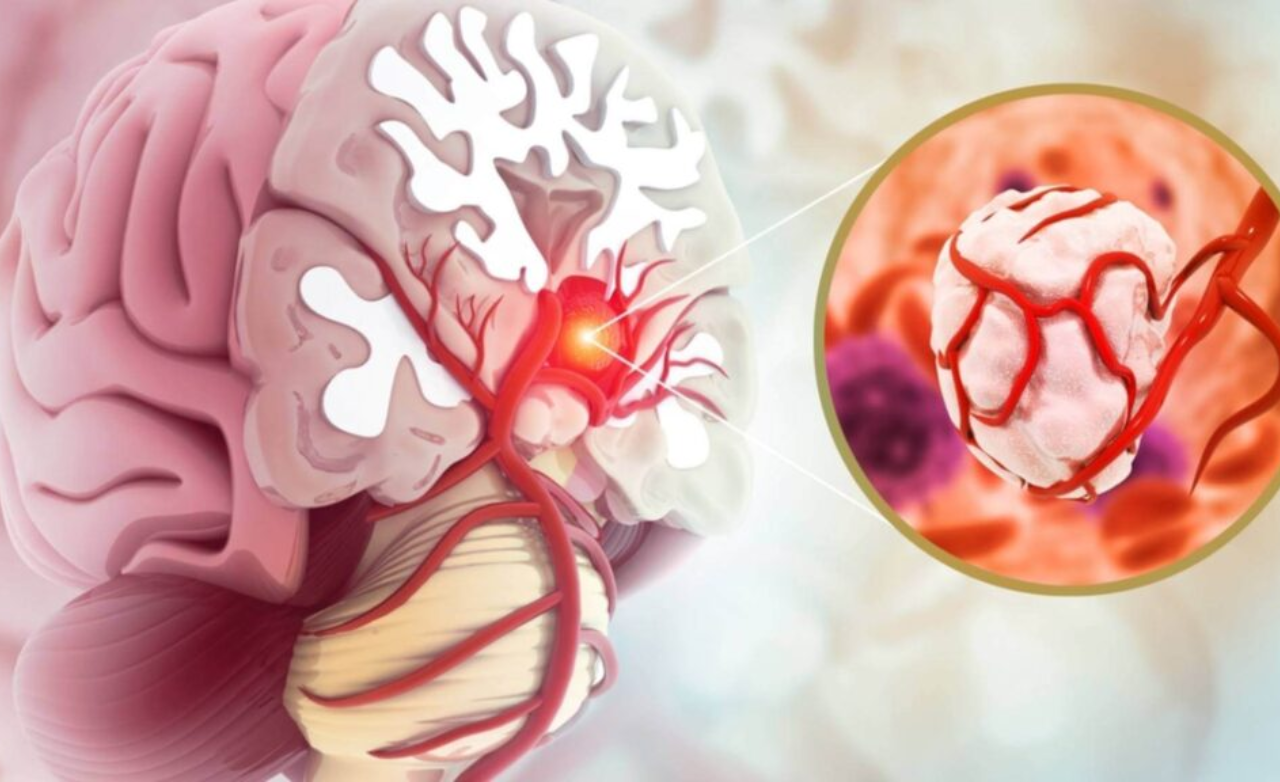

A bulging, weakened blood vessel in the brain that may rupture, causing life-threatening bleeding, headaches, neurological deficits, or stroke.